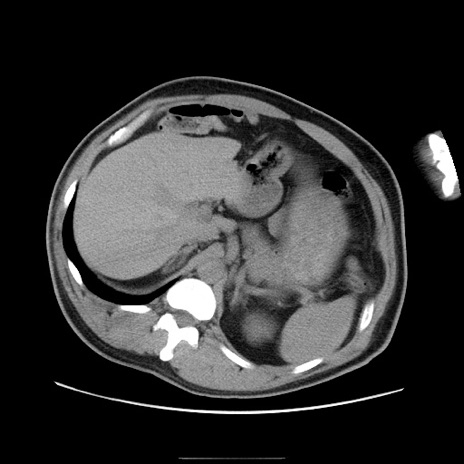

冠状断像